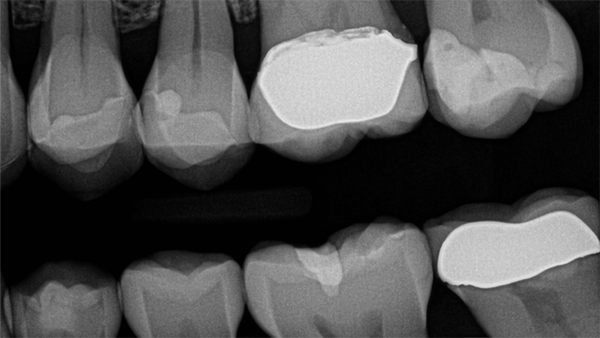

Fig 4. Preoperative visual.

Figure 4

Fig 5. Preoperative radiograph.

Figure 5

When performing multiple adjacent restorations, preliminary assessments must be made to achieve a successful contact. First, a dental professional must use visual (Figure 4) and radiographic analysis (Figure 5) to establish the location and extent of the caries and assess the adjacent teeth for normal anatomy. Protection of the adjacent teeth during preparation to preserve anatomy and maintain a smooth surface must be ensured, which will help in reducing plaque accumulation. Afterwards, teeth should be prepared with an efficient sequence, and the type and location of matrices should be determined. Next, sequences of steps should be established if adjacent contacts must be restored to ensure that successful anatomic contours are reconstructed. Then a pre-etch technique should be used to optimize the seal of the occlusal portion of the restoration. An adhesive seal of the resin to the tooth structure may be created with a reliable adhesive system, and sectional matrices can be used to form tighter contacts in posterior resin restorations.